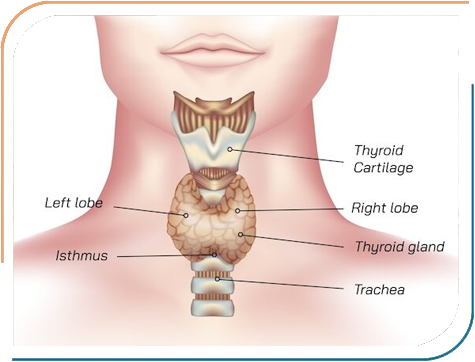

Dr. Jhala's expertise encompasses a wide range of paediatric endocrine disorders, including Growth abnormalities, Childhood Diabetes, Thyroid disorders in Children, Puberty-related concerns, Bone diseases and many other hormonal conditions in Children. She is dedicated to diagnosing and treating conditions such as Type 1 diabetes, Growth hormone deficiencies, and early or delayed puberty, all aimed at helping children lead healthier, more fulfilling lives. Her approach combines thorough clinical evaluation with the latest medical advancements, ensuring comprehensive care tailored to each child's needs.